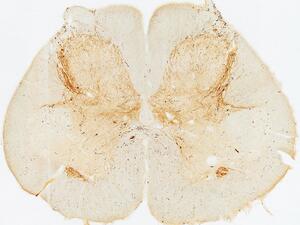

Sleep Disordered Breathing

Our major goal is to identify circuits in the brainstem modulate the control of upper airway muscles, breathing and arousal during sleep, as relevant for sleep apnea. Similar to the gait line, we determine which neuropathologies affect these circuits (in human tissues), how dysfunction in these circuits results in different types of sleep disordered breathing, and how circuit modulation can correct these symptoms.